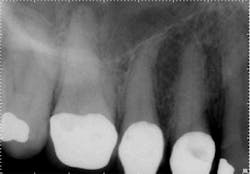

However, when the anatomy is the most complicated with multiple curves or the smallest canals, a different file system might be a better choice (Figs. 3 and 4). Although almost all root canals can be treated with WaveOne, in certain anatomies the root canal procedure is actually easier and more efficient when utilizing a file system that has more tip sizes and taper choices and ultimately requires more files. Vortex Blue (Dentsply Tulsa Dental Specialties), with its incredible resistance to cyclic fatigue and reduced shape memory, is an ideal file choice in this clinical situation. Vortex Blue files have tip sizes ranging from ISO 15-50 and tapers of 0.04 and 0.06. This results in great flexibility to treat the most complicated canal anatomies — flexibility not only in the file itself, but also in the size and taper choices that are available. However, to appreciate the metallurgical advantages of the Vortex Blue files, it may be necessary to spin four or as many as six files per canal.

Fig. 3: Preoperative anatomy of tooth No. 31 shows a double curve in the mesial root canal. The size, length and taper of the root suggest a file system with multiple tip and taper choices would be most suitable.

Fig. 4: A glide path was established with a 15/0.04 Vortex Blue rotary file in conjunction with size 10 hand files. Vortex Blue files were then used in sequence until a final shape of 30/0.04 was achieved in the mesial root and 30/0.06 in the distal root.